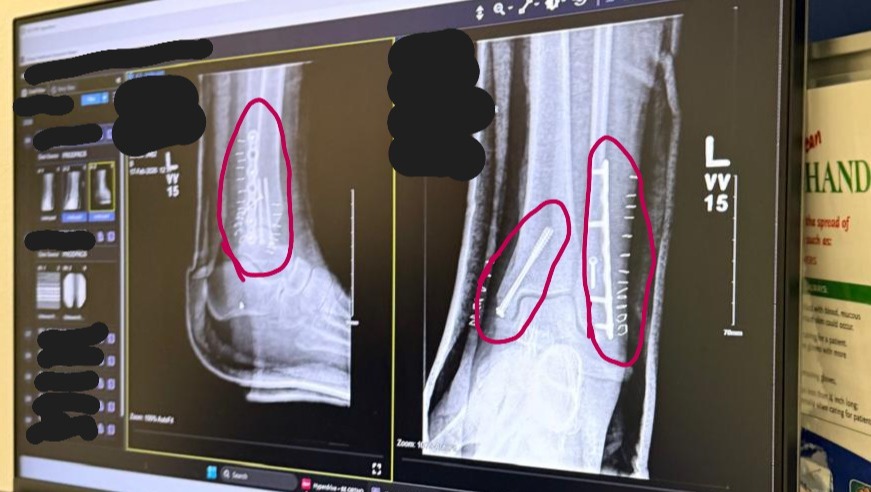

• On January 26th, 2026, a month after her mom's passing, Karine slipped on some ice, breaking her ankle in 3 places.

• She works in a kitchen, on her feet, and has therefore been unable to work ever since. She had surgery on February 5th, 2026, where some screws were used to heal the fractures.

• Once the surgery will have healed , and she's able to put pressure on her foot, she'll then start rehab. We are awaiting word on if the surgery, rehab and time off of work, which should be about 2 months, will be covered by insurance.

• Le 26 janvier 2026, un mois après le décès de sa mère, Karine a glissé sur de la glace et s'est fracturé la cheville à trois endroits.

• Elle travaille habituellement debout dans une cuisine, et se trouve donc en arrêt de travaille depuis. Elle a subi une intervention chirurgicale le 5 février 2026, au cours de laquelle des vis ont été utilisées pour consolider ses fractures.

• Une fois la cicatrisation terminée, et qu'elle pourra s'appuyer sur son pied, elle débutera les traitements de réadaptation.

• Nous attendons des nouvelles à savoir si sa chirurgie, sa réadaptation et son congé médicale qui pourrait durer deux mois, seront couvert par l'assurance.